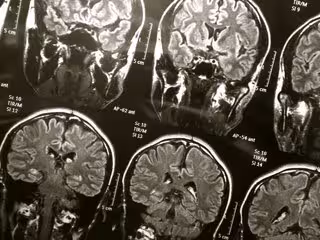

El colesterol cerebral, asociado con mayor riesgo de enfermedad de Alzheimer

Cerebro

FLICKR/WYINOUE - Archivo